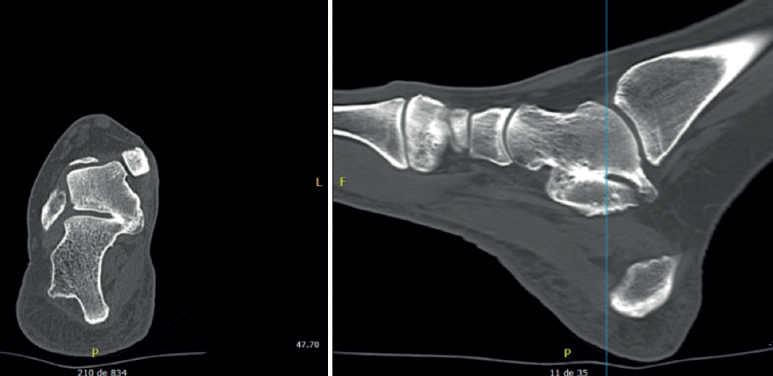

Figura 5. En la proyección axial se intuye la falta de paralelismo entre las superficies articulares. A: en la tomografía axial computarizada se aprecia coalición bilateral, con el drunken waiter sign, en uno de ellos (la bandeja del camarero se inclinaría); C: en la reconstrucción tridimensional se aprecia importante deformidad en el sustentaculum, donde el paciente refería dolor y deformidad.

Drunken waiter sign o signo del “camarero borracho” (Figura 5): si se aprecia en las radiografías axiales del calcáneo de Harris un ángulo superior a 20° entre la superficie del sustentaculum y la posterior, se sospechará una coalición, con una sensibilidad del 72% y una especificidad del 94% que se debe confirmar en cortes coronales de TAC.